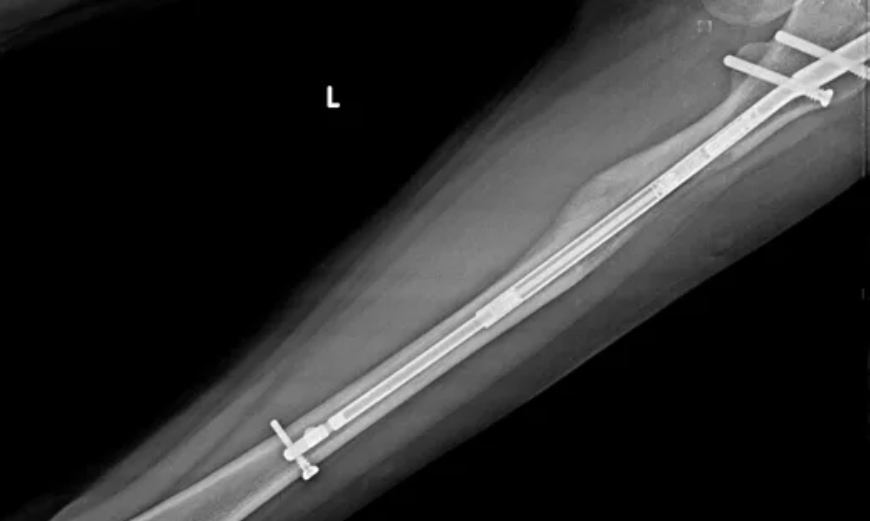

Boy uzatma ameliyatlarında kemiği içeriden sabitlemek için kullanılan ileri teknolojiye sahip bir sistemdir. Titanyum alaşımından üretildiği için yüksek dayanıklılığa sahiptir ve vücut dokuları ile uyumu oldukça iyidir. Bu sayede uzun süre vücutta kalmasında herhangi bir sakınca oluşmaz. Çivinin boyutu, hastanın kemik yapısına göre belirlenir ve genellikle 8.5 mm, 10.7 mm, 11.5 mm veya 12.5 mm seçenekleri kullanılır. Doktor, röntgen görüntülerini değerlendirerek kemik kalınlığı ve yapısına en uygun ölçüyü seçer.

Ameliyat sırasında intramedüller çivi cerrahi olarak kemik içerisine yerleştirilir. Bu işlem, kemiğin dayanıklılığını koruyarak uzatma sürecinin stabil ve güvenli şekilde ilerlemesini sağlar. Hafif ancak güçlü titanyum yapısı sayesinde hastalar günlük yaşamlarında daha rahat hareket edebilir ve uzama süreci kemik içinde konforlu şekilde devam eder. Bu da komplikasyon riskinin minimum seviyede tutulmasına yardımcı olur.

İlk olarak hastanın genel sağlık durumu değerlendirilir ve gerekli röntgen çekimleri yapılır. Bu incelemeler sonucunda kemik yapısına en uygun çivi boyutu belirlenir. Planlama süreci, hastanın kemik yapısı ve hedeflenen uzama miktarına göre kişiye özel olarak yapılır.

Çivinin cerrahi olarak yerleştirilmesi:

Ameliyat genel anestezi altında gerçekleştirilir. Kemik üzerinde küçük bir kesi yapılarak uzama için gerekli alan oluşturulur. Daha sonra seçilen Precice 2 çivisi kemik içine yerleştirilir ve güvenli şekilde sabitlenir.